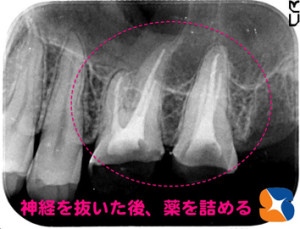

上の奥歯2本から神経を抜く

コラム「上の奥歯2本から神経を抜く」の画像